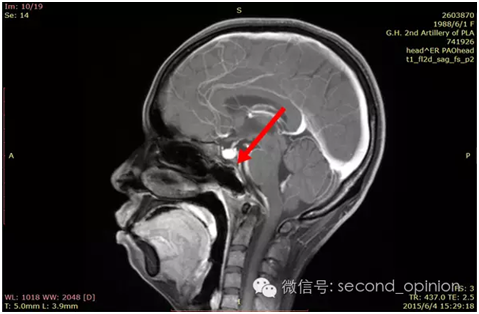

质子治疗前

2015年1月25日 对比质子治疗之前增强核磁共振影像无明显变化,脊索瘤放疗后变化缓慢,建议3月后继续复查。